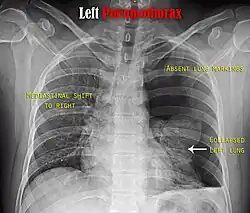

-

Anteroposterior inspired X-ray, showing subtle left-sided pneumothorax caused by port insertion -

Lateral inspired X-ray at the same time, more clearly showing the pneumothorax posteriorly in this case -

Anteroposterior expired X-ray at the same time, more clearly showing the pneumothorax in this case -

Chest X-ray showing a pneumothorax on the right (left in the image), where the absence of lung markings indicates that there is free air inside the chest -

Chest X-ray showing the features of pneumothorax on the left side of the person (right in image)